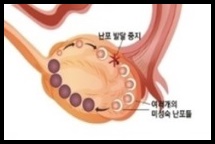

다낭성 난소증후군

난소 내 성장난포가 정상범위보다

많이 존재하는 질환으로

원인은 정확하지 않으나

난소의 호르몬 불균형으로 추정하며

가임기 여성의 발병률이 5~10% 정도로

흔한 질병이며